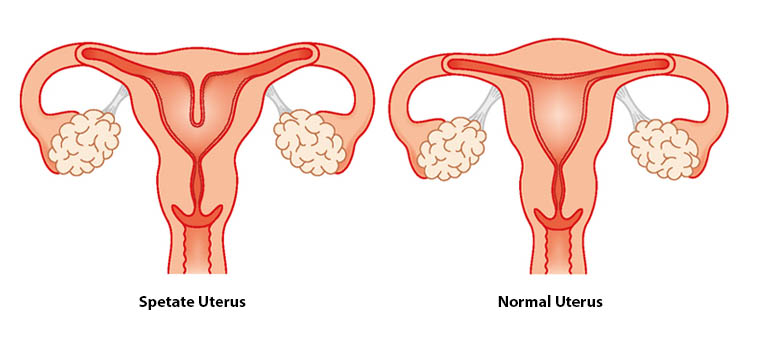

Women’s health requires a thoughtful and personalized approach at every stage of life. Our gynecology services are designed to diagnose, manage, and treat a wide range of gynecological conditions with accuracy, compassion, and advanced medical expertise. We provide comprehensive care for issues such as menstrual irregularities, pelvic pain, hormonal imbalances, reproductive health concerns, infections, fibroids, ovarian cysts, and other common and complex gynecological conditions.

Using modern diagnostic techniques and evidence-based treatments, our team focuses on identifying the root cause of symptoms rather than just managing them temporarily. Each patient receives an individualized treatment plan based on her medical history, symptoms, and overall health goals. From routine check-ups and preventive screenings to specialized treatments and minimally invasive procedures, we aim to deliver safe and effective care tailored to each individual.